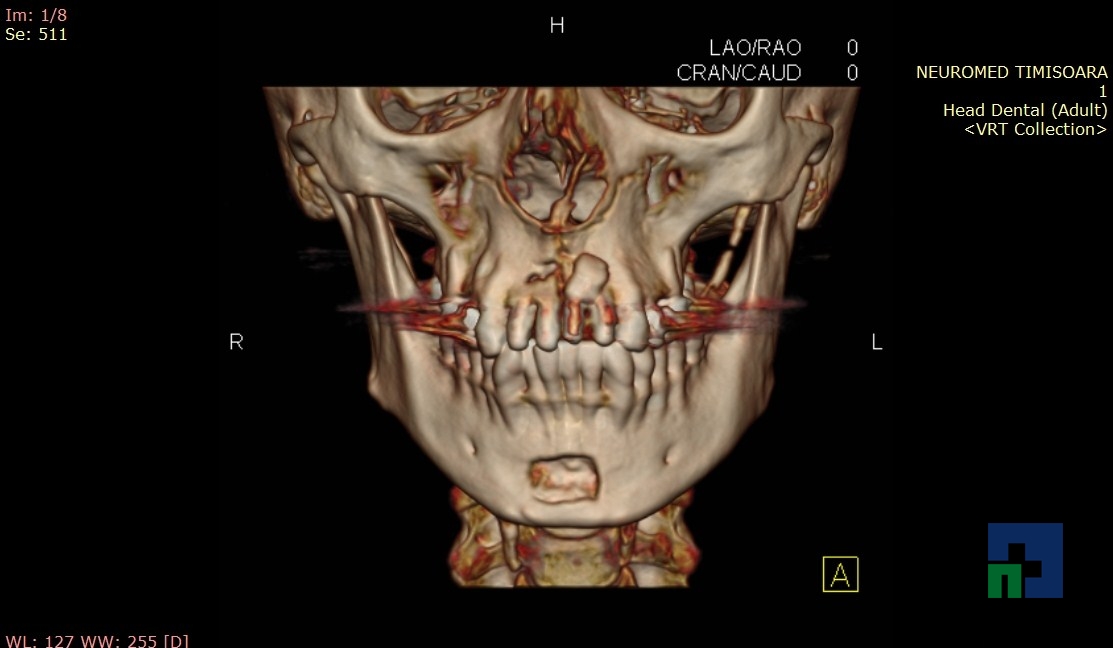

- Diagnosticul fracturilor:

- Unice

- Multiple

- Cu înfundare

- Complexe cranio-sinusale

- Complexe cranio-etmoidale

- Complexe cranio-orbitare

- Complexe cranio-faciale